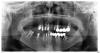

Teethless Опубликовано 29 января, 2013 Поделиться Опубликовано 29 января, 2013 (изменено) Добрый день! Нуждаюсь в нескольких имплантах и подсадке костной ткани. Предлагают установить 8 шт. сразу с одновременной подсадкой, а старый воспалённый и гноящийся имплант удалить позже. Есть сомнения. что это правильно. Спасибо за ответы. С уважением, Teethless. Изменено 29 января, 2013 пользователем Teethless Ссылка на комментарий

Teethless Опубликовано 29 января, 2013 Автор Поделиться Опубликовано 29 января, 2013 для интернет консультации нужны снимки. Есть ортопантомограмма Ссылка на комментарий